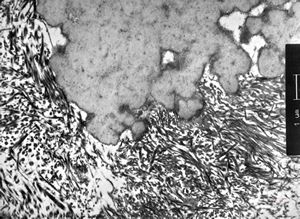

M,7y. | epidermolysis bullosa (dystrophic type) - oral mucosa